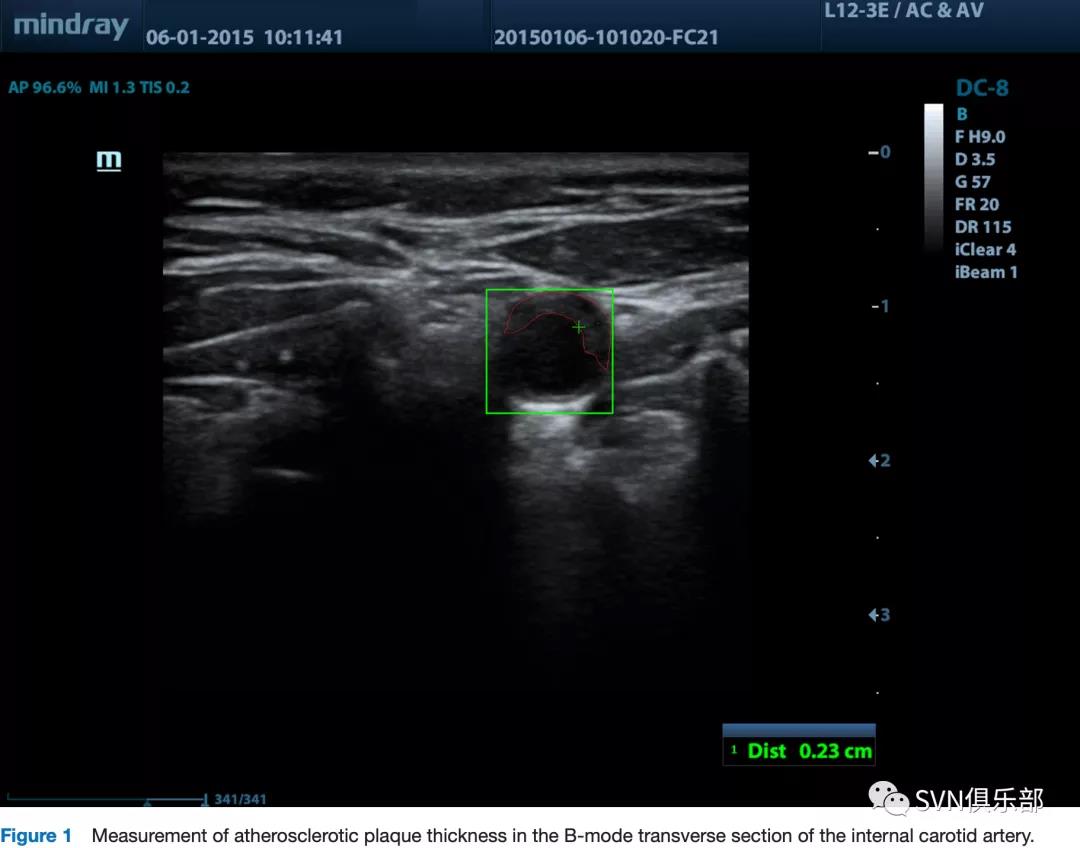

颈动脉斑块进展可增加卒中风险,本研究旨在明确将预防性治疗调整为“治疗动脉而非危险因素”的策略后,影响颈动脉斑块厚度进展的因素,即根据动脉粥样硬化的进展改变治疗。在3年内完成超声检查的研究参与者被纳入研究,每隔6个月对颈动脉进行一次多普勒超声检查,并测量颈动脉斑块厚度。斑块厚度测量误差(σ)设置为3 SD。仅明显稳定和进展的斑块(分别定义为初始和最终斑块厚度测量值之间的差异<σ和>2σ)被纳入分析。采用单因素和多因素Logistic回归分析以明确影响斑块进展的因素。

研究共纳入1391例患者(男性466例,年龄67.2±9.2岁)。在255例(18.3%)患者中检测到至少一根颈动脉中的进展性斑块。年龄较大、男性、斑块较厚、冠心病、血管手术/支架置入手术史及吸烟在进展性斑块患者中更常见(p<0.05 in all cases)。多因素Logistic回归分析仅明确了斑块厚度(OR 1.850 for left side, 95%CI 1.398 to 2.449; and OR 1.376 for right side, 95%CI 1.070 to 1.770)是影响斑块进展的独立因素。